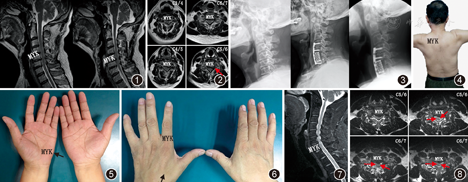

患者(病例3)男,63岁,以"左上肢疼痛、无力8个月余,加重伴肩关节功能障碍2个月余"收入院,患者于8个多月前无明显诱因出现左上肢疼痛,以肩部、上臂、前臂外侧为主,随着病程的延长,逐渐出现左上肢麻木、肌力下降,2个月前肌力明显下降,伴左侧肩部活动受限,以外展、前屈为主。查体:步态稳,颈椎活动轻度受限,无压痛,颈部过伸,左侧三角肌明显萎缩,肌力3-级(MMT分级),左侧肩关节外展受限,MRI示C4/5、C5/6、C6/7椎间盘突出(图1,图2);肌电图显示:左上肢神经源性损害之电生理改变,以C5、C6节段支配肌肉为主,考虑颈神经根受损可能。入院诊断为"肌萎缩型颈椎病",进一步完善检查,于全麻下行"颈前路减压植骨融合内固定术"(图3)。术后颈托制动3个月,术后3个月,左上肢无力明显好转,左侧肩部活动改善,三角肌萎缩轻度改善(图4);术后10个月,左上肢肌力恢复(略差于右侧)(图5,图6,图7,图8)。